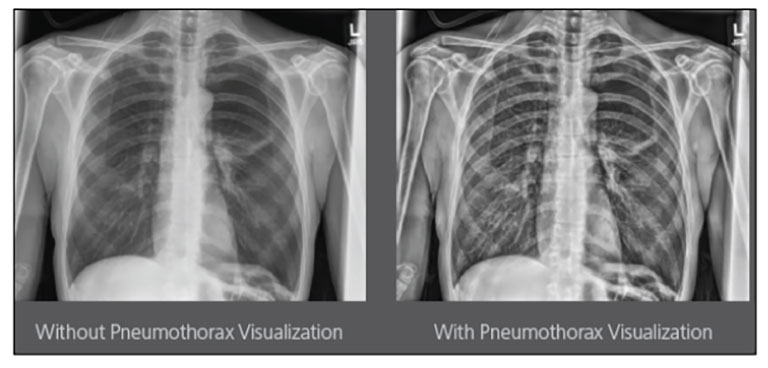

Carestream Introduces New Software Update to Boost Diagnostic Accuracy

Carestream today announced the latest update to its Image Suite V4 Software, MR 11: a series of enhancements to help improve customer confidence and increase diagnostic accuracy [...]

CARESTREAM Image Suite V4 MR11 has set a new standard for workflow efficiency, offering a robust set of features and functionalities to enhance clinical confidence in healthcare professionals. Using an auto-generated companion image from a single exposure, leverage a range of image processing options to increase diagnostic accuracy and enhance patient care.